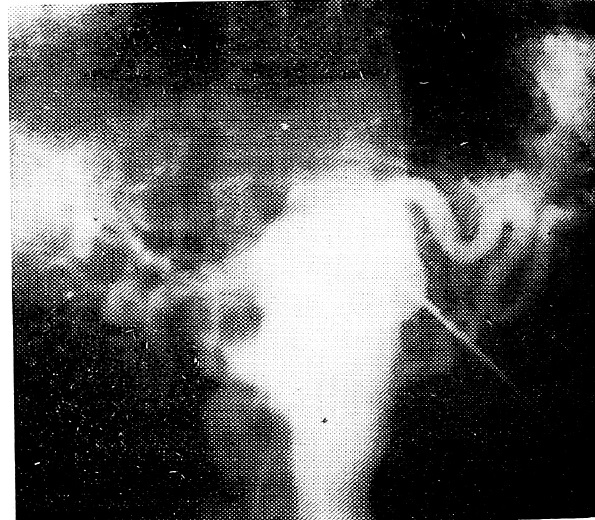

У одного больного на экскреторной урограмме констатирована нидронефротическая трансформация почки справа. На аортограмме определялось наличие добавочной артерии, отходившей непосредственно от аорты. Оба сосуда на ангиограмме имели одинаковые размеры и по своему ходу перекрещивались. Из них артерия, подходившая к нижнему полюсу почки, вызвала гидронефротическую трансформацию почки за счет перекреста прилоханочного отдела мочеточника (рис. 1). Полученные данные в дальнейшем были подтверждены в процессе операции.

Рис. 1. Нижнеполюсная добавочная почечная артерия, берущая начало от общей печеночной артерии.